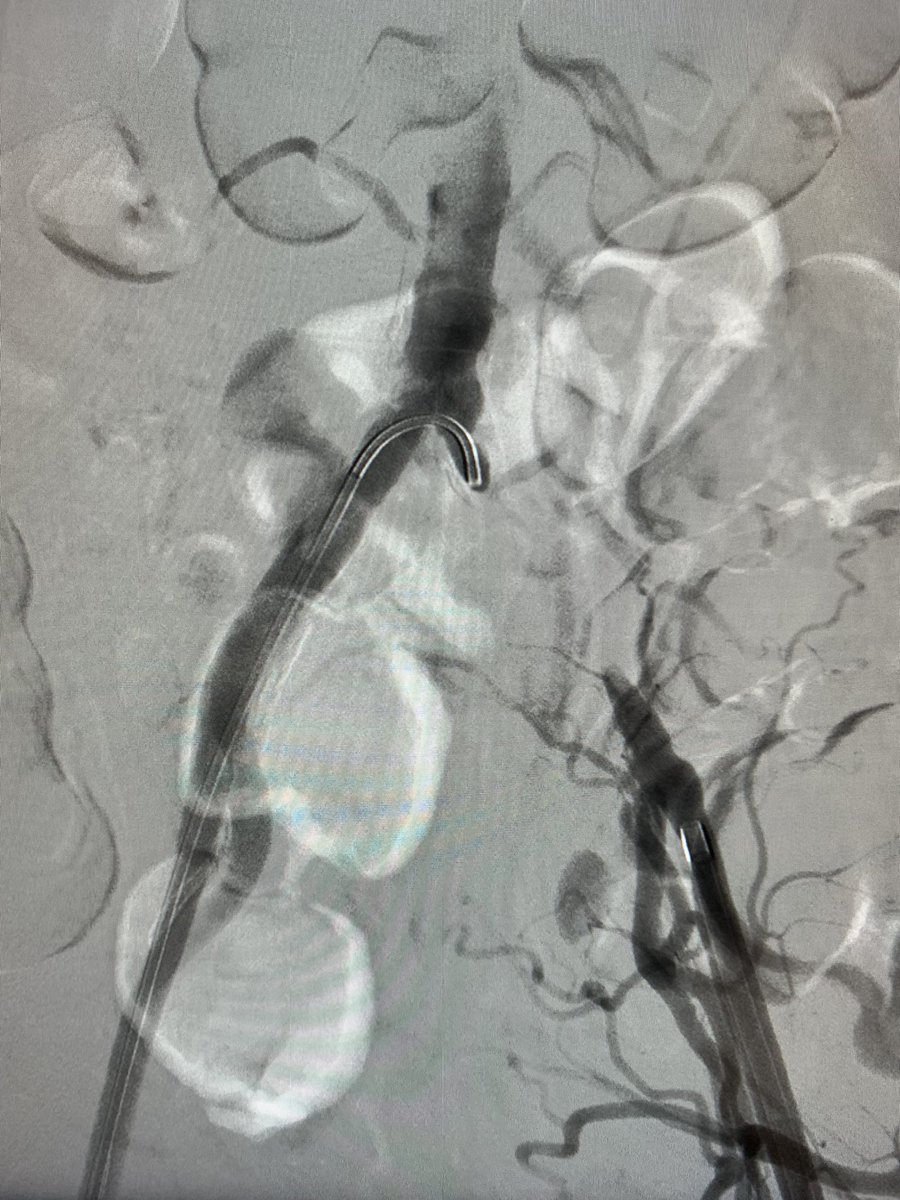

.@LucasRCmd, MPH; @HiroSparks, MD; Kara E. Masterson, MSN, NP; Scott J. Genshaft, MD; @AdamPlotnik, MD; and Siddharth A. Padia, MD, contributed to this open access article. See what they've been working on! brnw.ch/21wPx6v